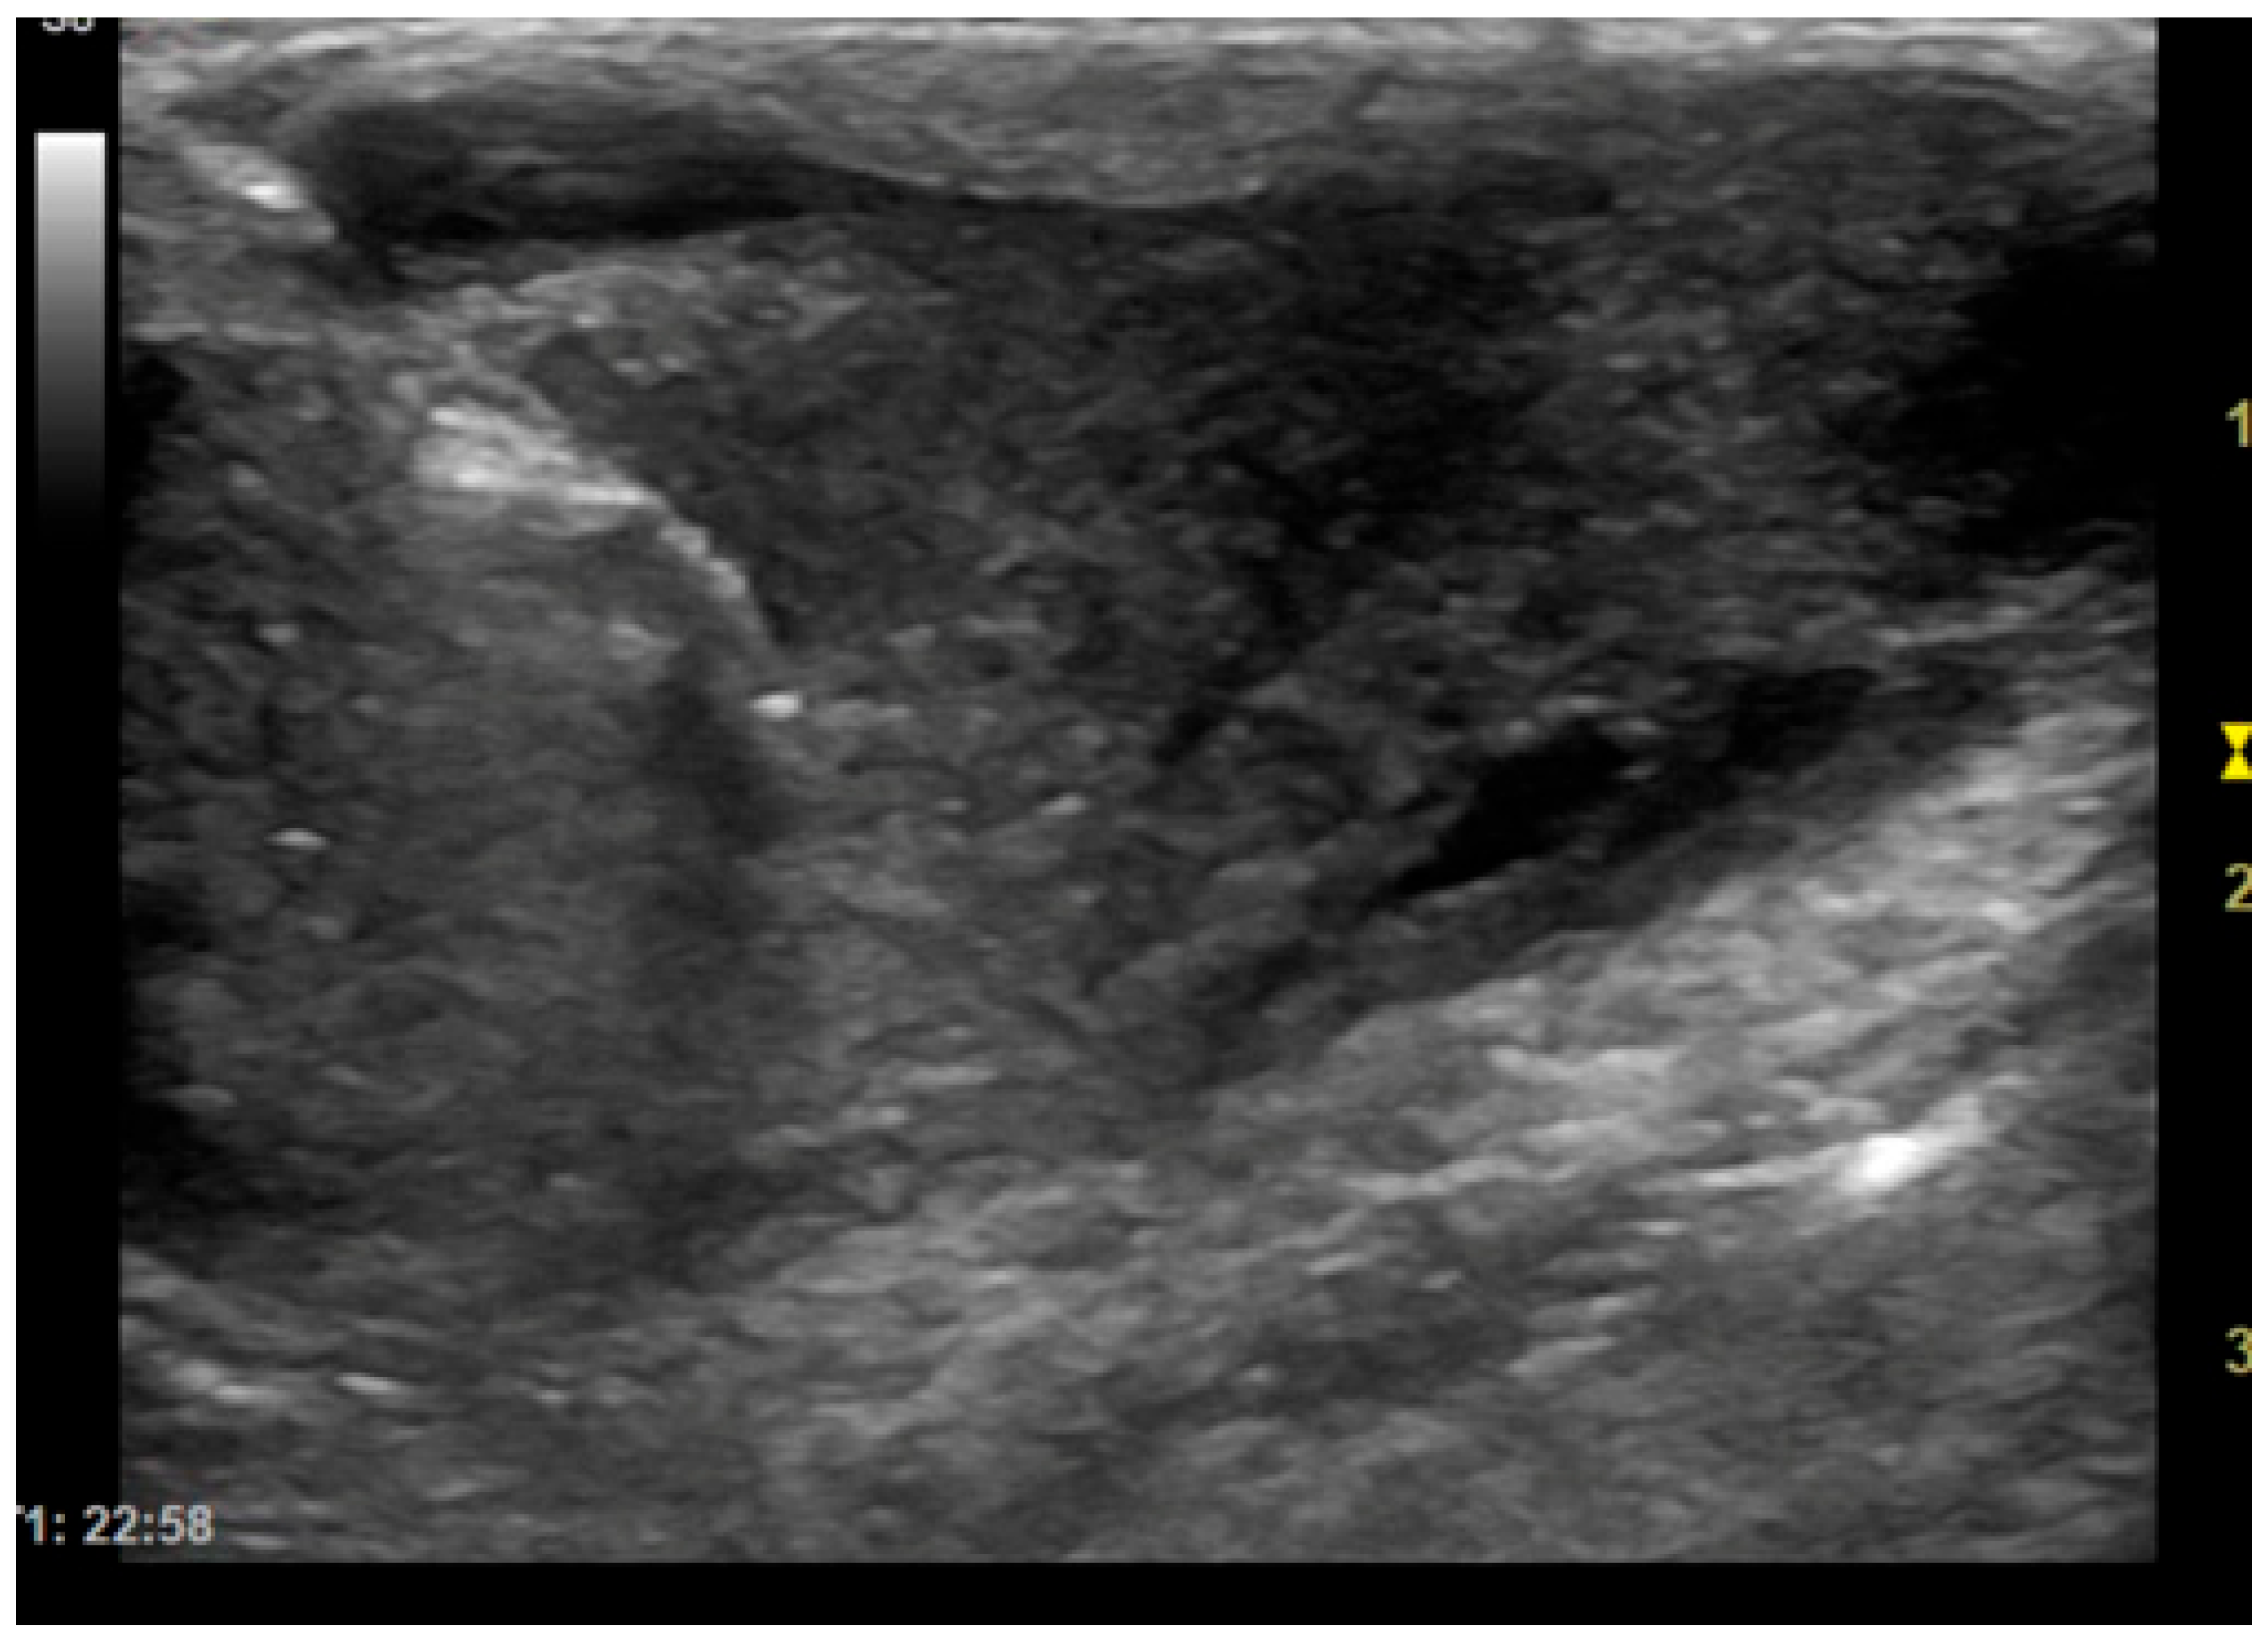

The patients included in the study underwent imaging-guided biopsies, specifically under US or CT guidance, of the masses under examination as shown in Figure 1 and Figure 2. Biopsy samples were collected using a semi-automatic spring-loaded tru-cut (14 G) in the case of soft tissue lesions and a bone needle (8–10 G) for bone tissue. These interventional diagnostic methods were performed after monitoring and anesthetizing the patient, under the continuous supervision of the anesthetist in charge. Trichotomy of the area of interest was performed, followed by surgical scrubbing with betadine and alcohol. Once the patient was prepared, a small incision was made with a number 11 scalpel blade on the skin surface, through which the tru-cut (14 G) or bone needle (8–10 G) was subsequently inserted. The biopsies were performed using ultrasound guidance or computed tomography, depending on the case, the location of the lesion and the availability of instruments.

Figure 3. Dog, Mixed breed, 8 y, spayed female. Percutaneous ultrasound-guided biopsy of liver mass. Final diagnosis: Well-differentiated carcinoma.

ROSE provides immediate feedback on sample adequacy, enabling a faster and more reliable diagnosis [10]. To increase the likelihood of obtaining diagnostic samples, multiple biopsies are usually performed on the same lesion. However, performing each biopsy, especially in dangerous anatomical locations, can cause complications. Therefore, the main objective of this study is to try to reduce the number of biopsies that need to be performed to obtain a diagnostic sample, thereby also lowering the risks for the animal. Analysis of the results of this study has shown that extemporaneous cytological examination can be useful for the purpose described above. In fact, out of 79 biopsies collected, extemporaneous cytological examination revealed cellularity in 81% of cases. The presence of representative cellularity in these samples made it possible to terminate the biopsy procedures. In the remaining cases, the lack of cellularity in the extemporaneous cytology suggested that further sampling should be carried out. Furthermore, it should be noted that in most of the samples in which no cellularity representative of the biopsied lesion was detected (25 out of 79), the cause was attributed to poorly stained and/or poorly fixed slides (technical problems), the presence of blood-contamination and poor cellularity due to the intrinsic nature of the sampled lesion. During the oncogenic process, blood may not arrive in sufficient quantities, causing an environment that is poor in oxygen (hypoxic) and nutrients (ischemic), which leads to necrosis, thus reducing the cellularity of the sample [13,14]. Furthermore, it is important to note that the interventional procedures in this study, excluding those performed with CT, were performed with 2D-mode ultrasound as shown in Figure 3. CT-guided biopsy sampling is, in fact, a procedure mainly indicated for bone lesions or lesions located in areas not easily accessible with US [6,15]. The relevance of this has been demonstrated in several studies reported in the literature as it can lead to several advantages. In the study by Vignoli et al. [16], in 2013, the importance of CT and guided biopsy in the staging of cancer patients was emphasized. In fact, although rare, muscular metastases can occur with different types of neoplasms. The most common sites of metastasis included the cervical, thoracic and lumbar paraspinal muscles, the chest wall, the scapular region, the hind limbs and, more rarely, the abdominal wall. The results highlight the importance of CT in the staging of cancer in dogs and cats, particularly in tumors with a high propensity for metastasis [14]. In this regard, for example, another study highlighted the frequency of muscle metastases in cases of hemangiosarcoma. Muscle metastases were found in 15/60 dogs (24.6%), all of which also had metastases in other organs. These data suggest that the use of whole-body CT and guided biopsy is essential in the staging of dogs with hemangiosarcoma, as muscle metastases may not be detected by clinical examination alone or by traditional imaging methods such as radiography and ultrasound [17]. Moreover, the intravenous injection of a non-ionic iodinated contrast medium provides additional vascular information about the lesion, allowing biopsy of viable tissue while avoiding major blood vessels and to sample the most representative portions of the lesion [8]. On the other hand, ultrasound is the method of choice in daily practice due to the wide availability of US equipment and its lower cost compared to CT [18]. In fact, as reported in some human literature, sampling of lung lesions visible with US is preferable [19]. Ultrasound can be used for real-time, multiplanar visualization, as well as for the accurate localization of target lesions that move with respiration. It also allows precise needle adjustment throughout all procedural steps. Additional advantages of ultrasound include the absence of radiation-related risks, its safety, speed, and cost-effectiveness [20]. Therefore, ultrasound has been recommended as an excellent option for guiding biopsies of peripheral pulmonary lesions [19]. Moreover, as demonstrated in some studies, the injection of contrast-enhanced ultrasound (CEUS) allows for the precise definition of the margins of the lesion, the identification of any necrotic areas, and the assessment of the distribution of vessels within it. The use of CEUS may be recommended to directly guide sampling procedures, improving the diagnostic success of cytological and histological examinations [21,22]. Therefore, paying particular attention to avoiding pre-analytical errors in the collection and/or preparation of slides, this method could prove particularly useful in interventional diagnostics.